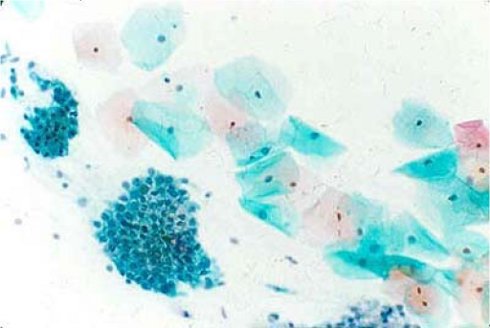

Mikroskopisches Bild normaler Schleimhautzellen des Gebärmutterhalses

Quelle:

Deutsches Krebsforschungszentrum Heidelberg, Forschungsschwerpunkt: Infektionen und Krebs, Prof. Dr. Gissmann